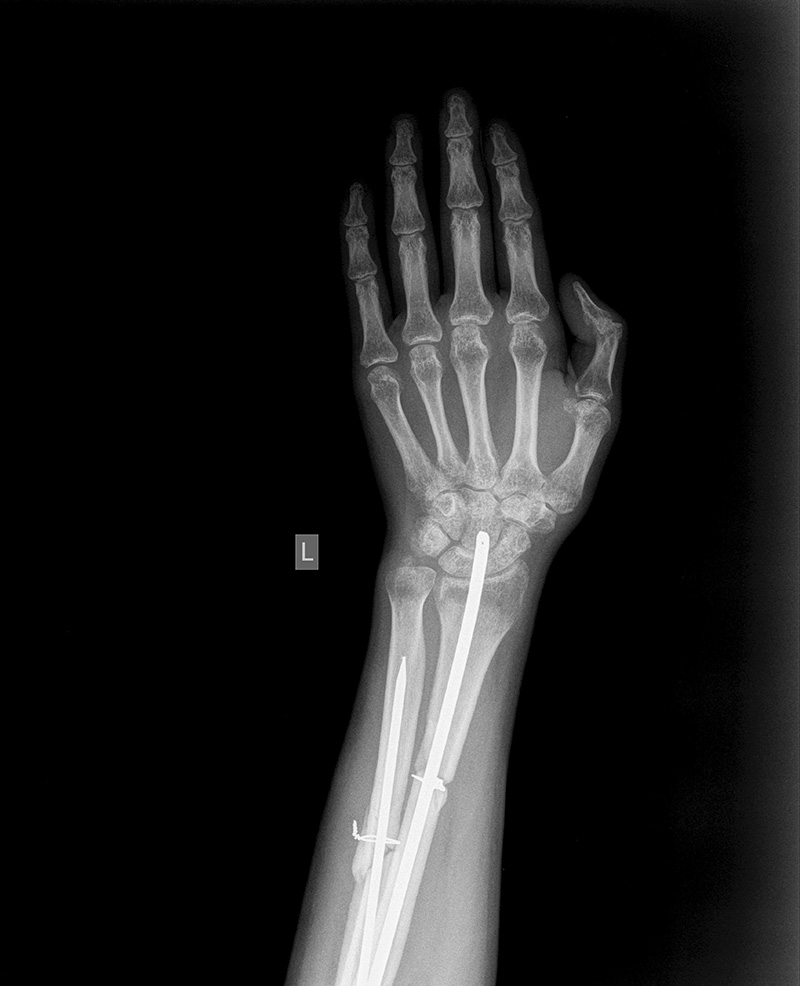

13. Рентгенография лучезапястного сустава-в с\3 костей предплечья имеется сопоставленный, фиксированный металлическими штифтами и проволокой слабо консолидированные переломы, лучезапястный сустав - околосуставной остеопороз с участками кистозной перестройки и участкам истончения коркового слоя, межсуставная щель несколько сужена, деструктивных изменений не выявлено.